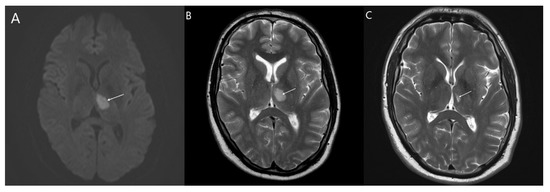

3.1. Pathogenic Mutation

3.1.1. Index Patients